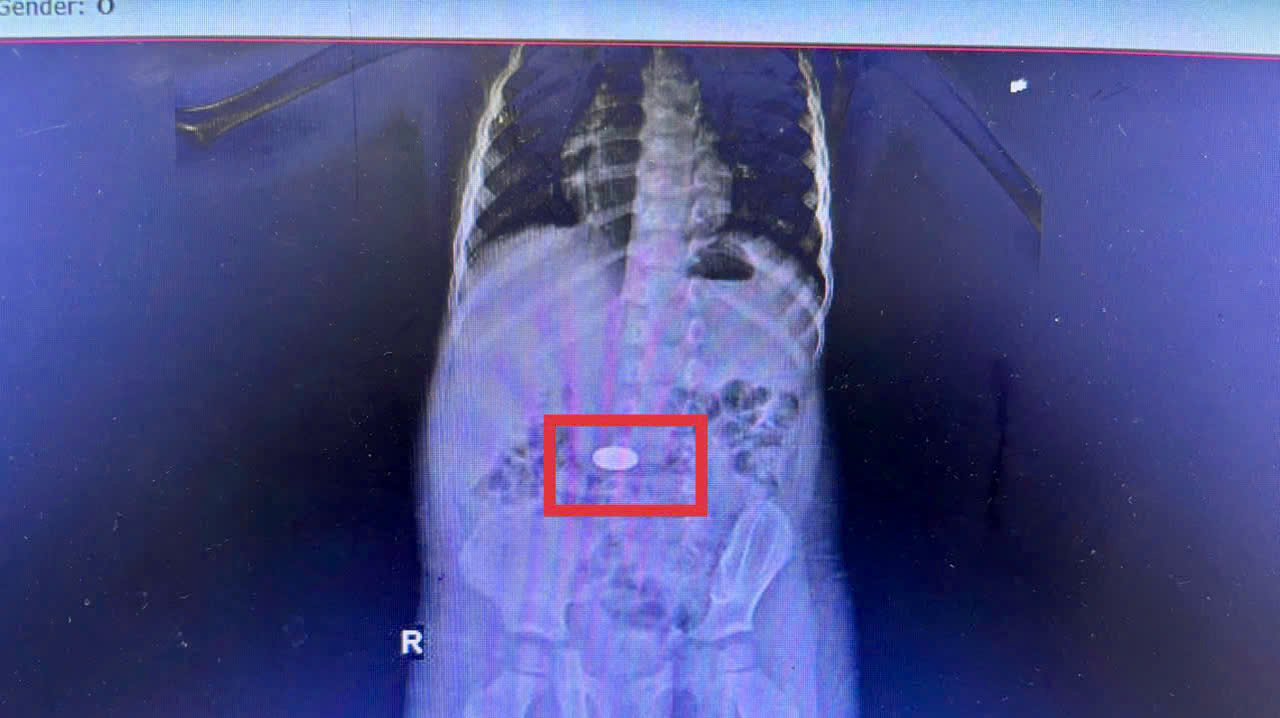

Một trường hợp điển hình là bé 3 tuổi ở xã Khánh Vĩnh, nhập viện tối ngày 25/11 trong tình trạng quấy khóc nhiều. Theo người nhà, buổi sáng cùng ngày bé vô tình nuốt phải đồng xu khi đang chơi. Chụp CT cho thấy dị vật nằm trong dạ dày. Các bác sĩ đã nhanh chóng tiến hành nội soi và lấy ra đồng xu vào rạng sáng 26/11. Bé hồi phục tốt và được xuất viện hôm sau.

Đồng xu nằm trong dạ dày trẻ